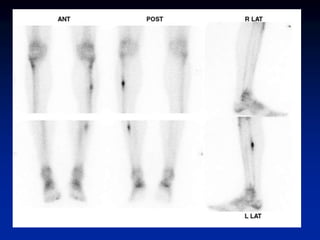

Shin Splints (Periostitis) •exercise induced pain along medial or posteromedial aspect of tibia • associated with increased tracer uptake • >1/3 of bone length • middle to distal tibia • usually bilateral (not necessarily symmetrical) • microperiosteal tears (via Sharpey’s fibers) • positive finding does not predict further injury

• 54.

• Hyperperfusion andhyperemia are typically present in acute stress fracture. • Unlike in stress fractures, angiograms and blood pool images are usually normal in shin splints. Delayed bone images reveal longitudinally oriented linear areas of increased uptake of varying intensity that involve one-third or more of the posterior tibial cortex